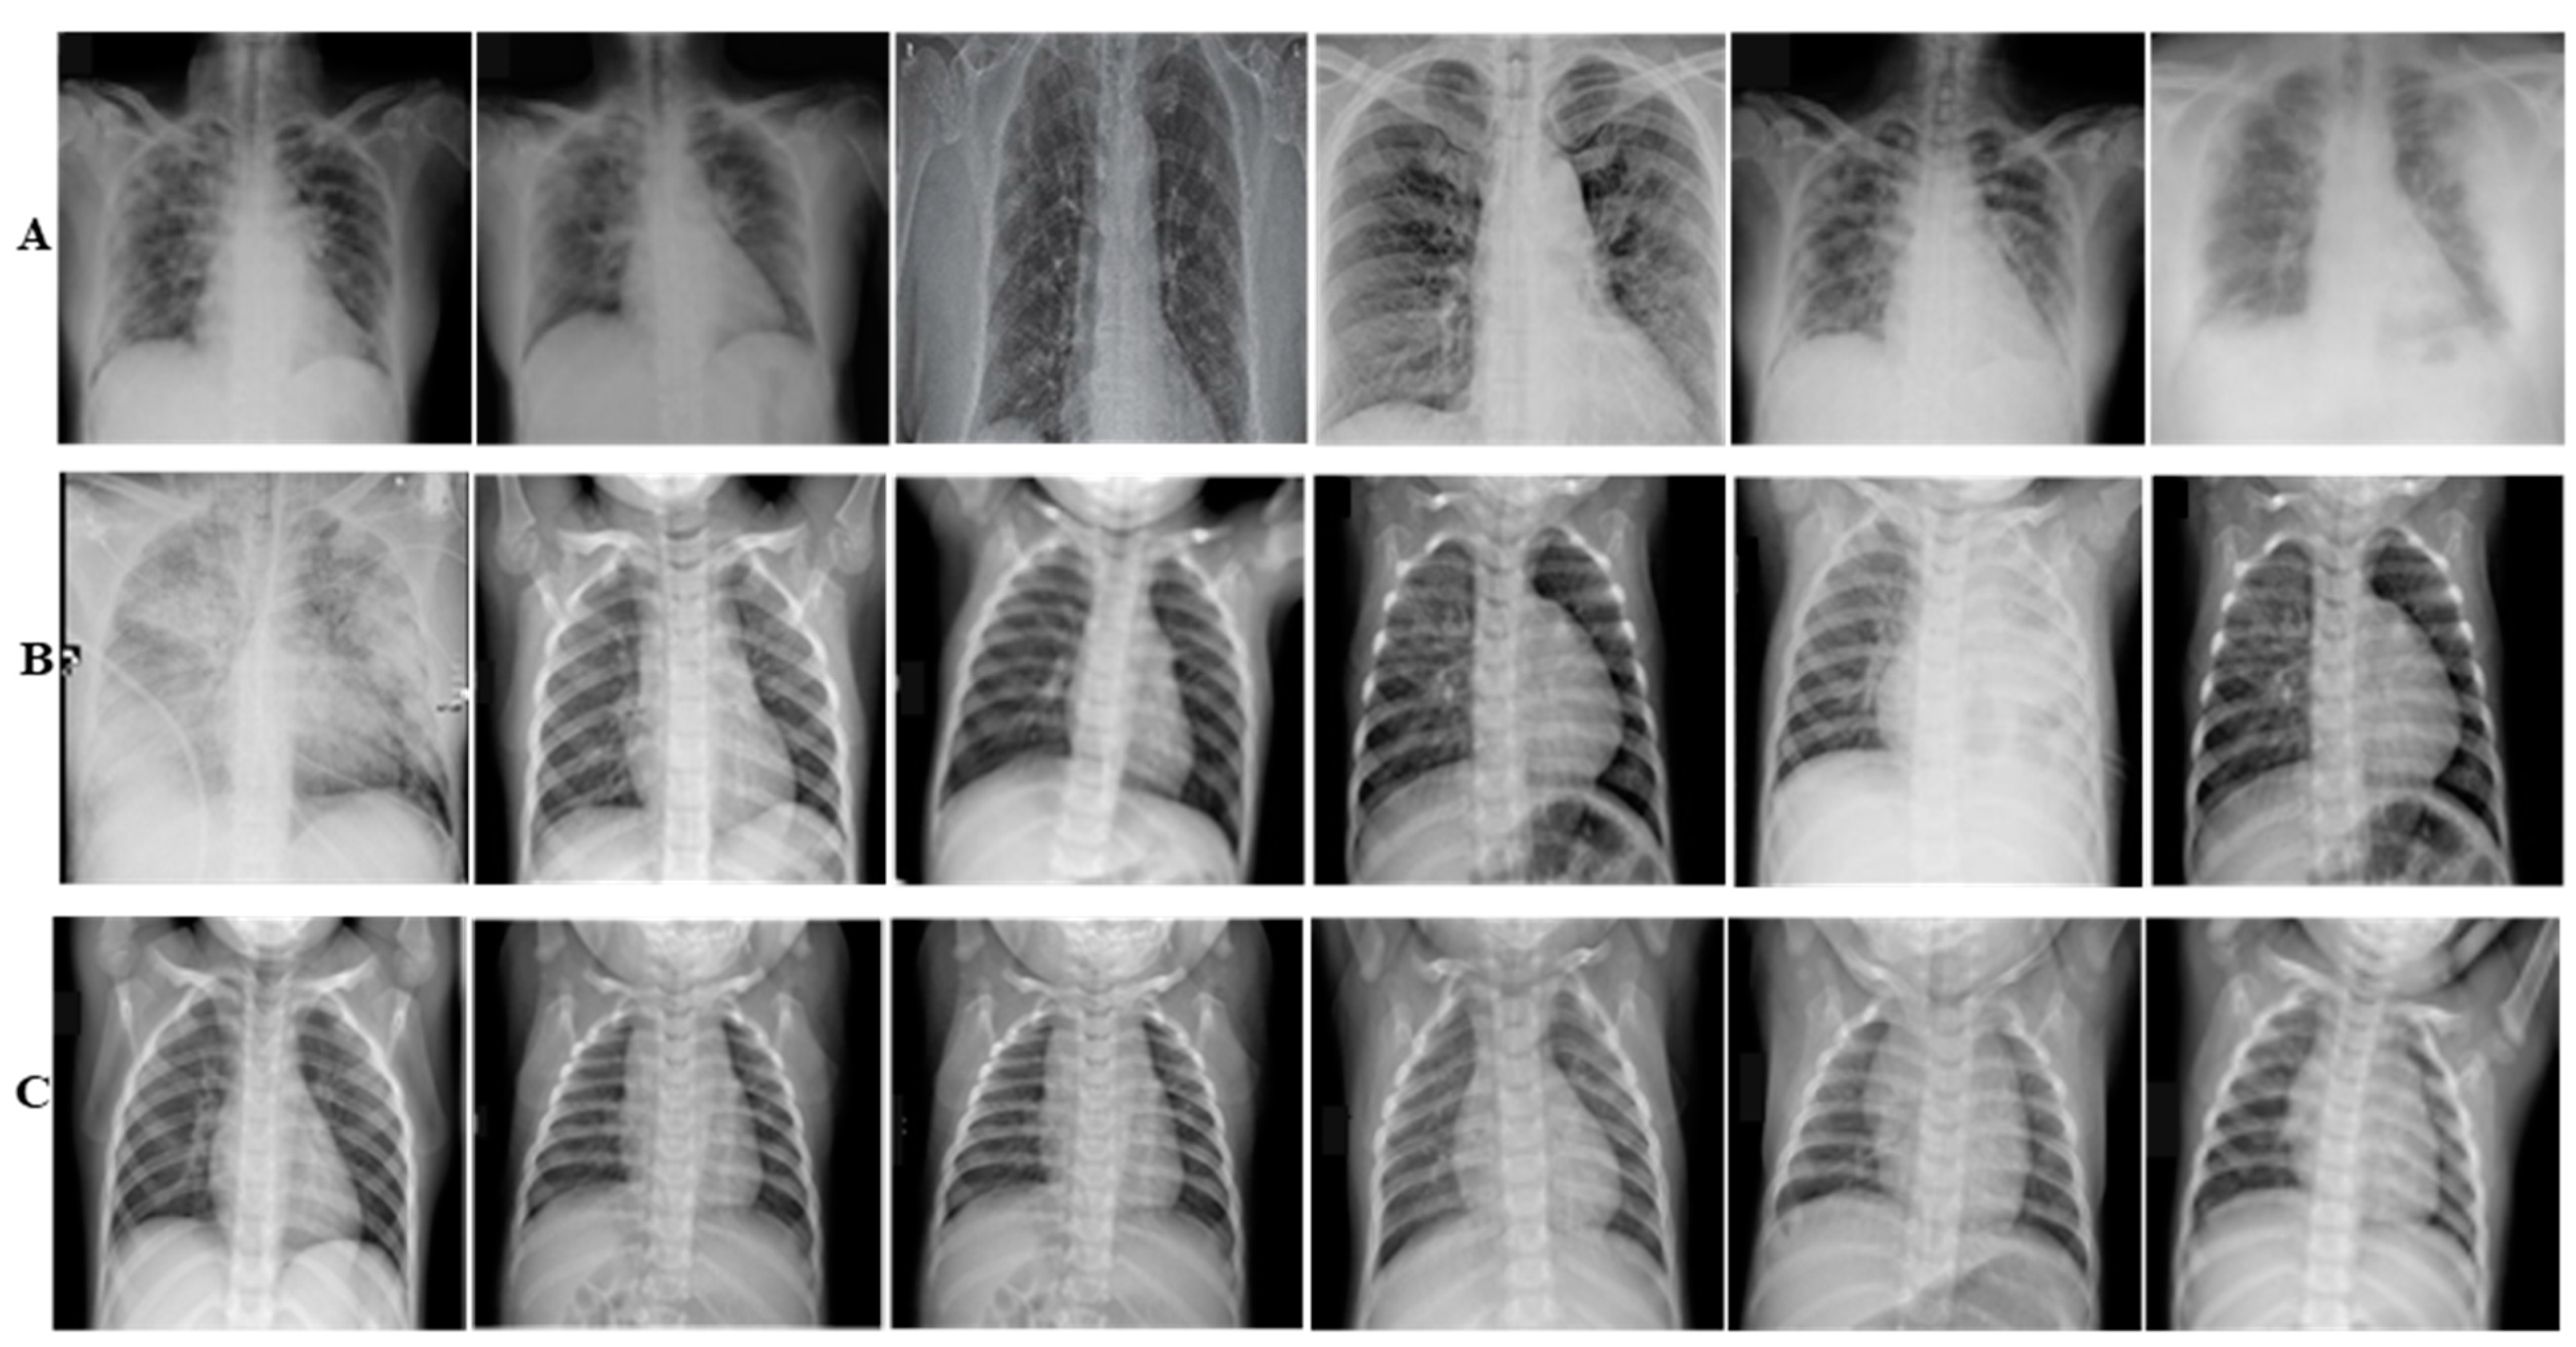

- Three different datasets from the publicly available chest X-ray images are generated (CoV-Healthy-6k, CoV-NonCoV-10k, and CoV-NonCoV-15k) and the performance of the proposed techniques is validated.

2.1. Dataset

2.1.1. CoV-Healthy-6k Dataset

2.1.2. CoV-NonCoV-10k Dataset

2.1.3. CoV-NonCoV-15k Dataset